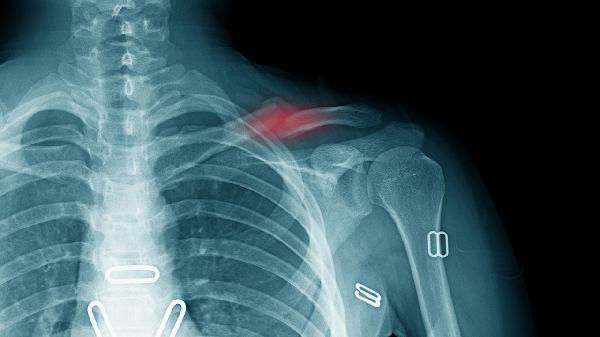

若僵硬伴随持续肿胀、皮肤发红发热或剧烈疼痛,可能提示感染或关节结构异常。少数情况下钢针拔除过早可能导致骨折端微动,刺激周围软组织形成瘢痕增生,此时需复查X线评估愈合情况。康复期间应避免暴力掰动关节,每日分次进行抓握、对指等针对性训练,配合超声波治疗或蜡疗可加速软组织恢复。